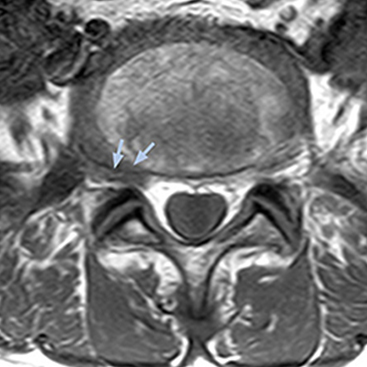

“For example, in sagittal images, when the presence of fat is observed in the intervertebral foramen, it suggests that there is a margin around the nerve. Similarly, the absence of fat indicates that the nerve is being compressed. So, we used to deduce nerve compression indirectly. With NerveVIEW, however, we can observe the condition of the nerves directly, regardless of the presence or absence of fat. We always prefer such direct observation of anatomy over having to make an inference about it.”

“Although symptoms of typical disc herniation and atypical hernia are very similar, the actual site of herniation is different. It is therefore important to characterize the nerve’s condition both inside and outside of the intervertebral foramina. “Conversely, if we see no abnormality in NerveVIEW, we can assume at least that there is no severe condition that requires surgery. Like this, it can help us avoid unnecessary surgery. NerveVIEW can have a tremendous impact in this way.”

“The intra-luminal signal of veins, especially around the intervertebral space, can be suppressed well with NerveVIEW. As a result, we can easily observe the detailed nerve structure around the posterior ganglion,” he says. “This is why we use 3D NerveVIEW for intraforaminal stenosis and extraforaminal stenosis/herniation (lateral disc herniation). On the other hand, if herniation is suspected to exist inside the dorsal root ganglion (DRG), balanced TFE or ProSet-FFE is applied. NerveVIEW is not suitable for evaluating the median type of herniation.” The SE-EPI DWI-based method for MR neurography works well for large FOV exams like whole-body MRI, but focal examination of nerves is often limited by the attainable spatial resolution (both inplane and slice direction) and geometric distortion. “3D NerveVIEW achieves higher in-plane resolution – close to our other routine spine sequences – and the source images can be used instead of adding a fat-suppressed T2-weighted sequence,” Tanji says.

“NerveVIEW can clearly show nerve courses and presence of nerve compression. However, when multiple abnormalities are seen, it can still be hard to determine which nerve is causing the symptoms,” says Dr. Yabuki. “In our experience so far, we see abnormal findings on NerveVIEW in about 70% of elderly patients. As the pain is usually caused by only one nerve, we thus need to find the exact corresponding nerve.” “With a nerve root block, the patient's pain is improved by infiltration of local anesthesia directly around the nerve root considered to be responsible. Knowing such nerve root block findings prior to image interpretation, helps to easily recognize abnormal findings on NerveVIEW as well. In other words, without a priori knowledge, based on symptoms and/or nerve root block findings, we must be aware of the possibility of overdiagnosis.”